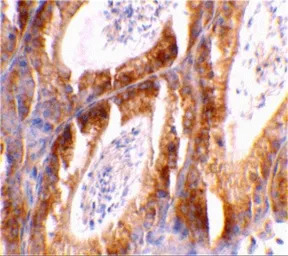

IHC-P analysis of mouse testis tissue using GTX31280 Bcl-G antibody.

Working concentration : 2 μg/ml